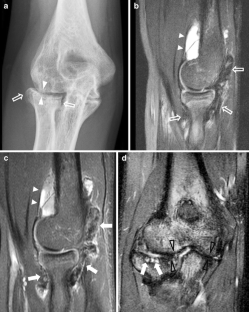

Fig. 2